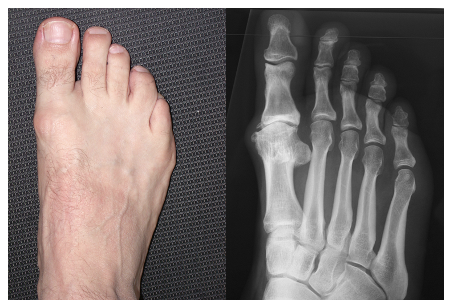

Mässig ausgeprägte Arthrose und überlanger erster Mittelfussknochen:

Entlastung des Gelenkes durch Verkürzen des ersten Mittelfussknochens. Hierbei wird nach dem Abtragen der Exostosen hinter dem Gelenkkopf eine V-förmige Durchtrennung des Knochens vorgenommen und der eine Schenkel um ca. 3-4mm verkürzt, was zu einer deutlichen Entspannung des Gelenkes und einer ebenso deutlichen Verbesserung der Beweglichkeit führt. Der Knochen wird mit einer Schraube wieder "zusammengesetzt", die nicht entfernt zu werden braucht. Dieser Eingriff führt auch zu einer Verbesserung auch der Gelenksverhältnisse, wie sich im Kontroll-Röntgenbild nach einem Jahr nachweisen lässt; allerdings lässt sich dabei die Arthrose nicht definitiv aufhalten.